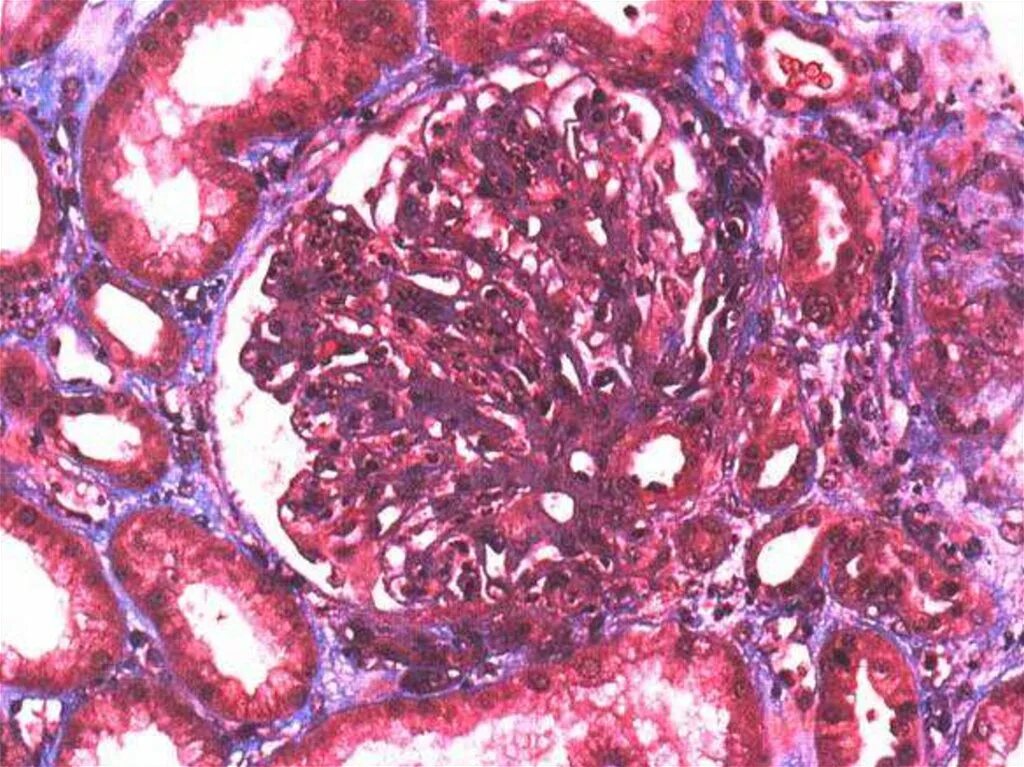

Интракапиллярный гломерулонефрит